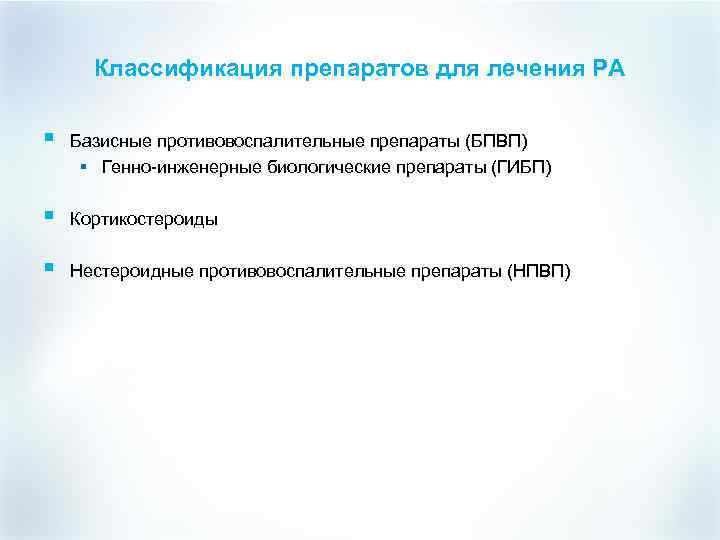

Классификация препаратов для лечения РА § Базисные противовоспалительные препараты (БПВП) § Генно-инженерные биологические препараты (ГИБП) § Кортикостероиды § Нестероидные противовоспалительные препараты (НПВП)

Классификация препаратов для лечения РА § Базисные противовоспалительные препараты (БПВП) § Генно-инженерные биологические препараты (ГИБП) § Кортикостероиды § Нестероидные противовоспалительные препараты (НПВП)